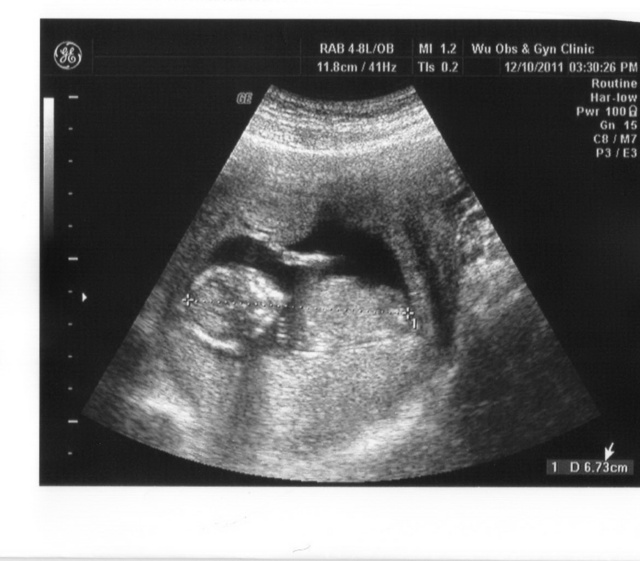

第13 ( 第四月 )

小果的手都已形成啦~~~~ 而且定是小女生~~~~

重量大概跟柳丁差不多唷~~~~